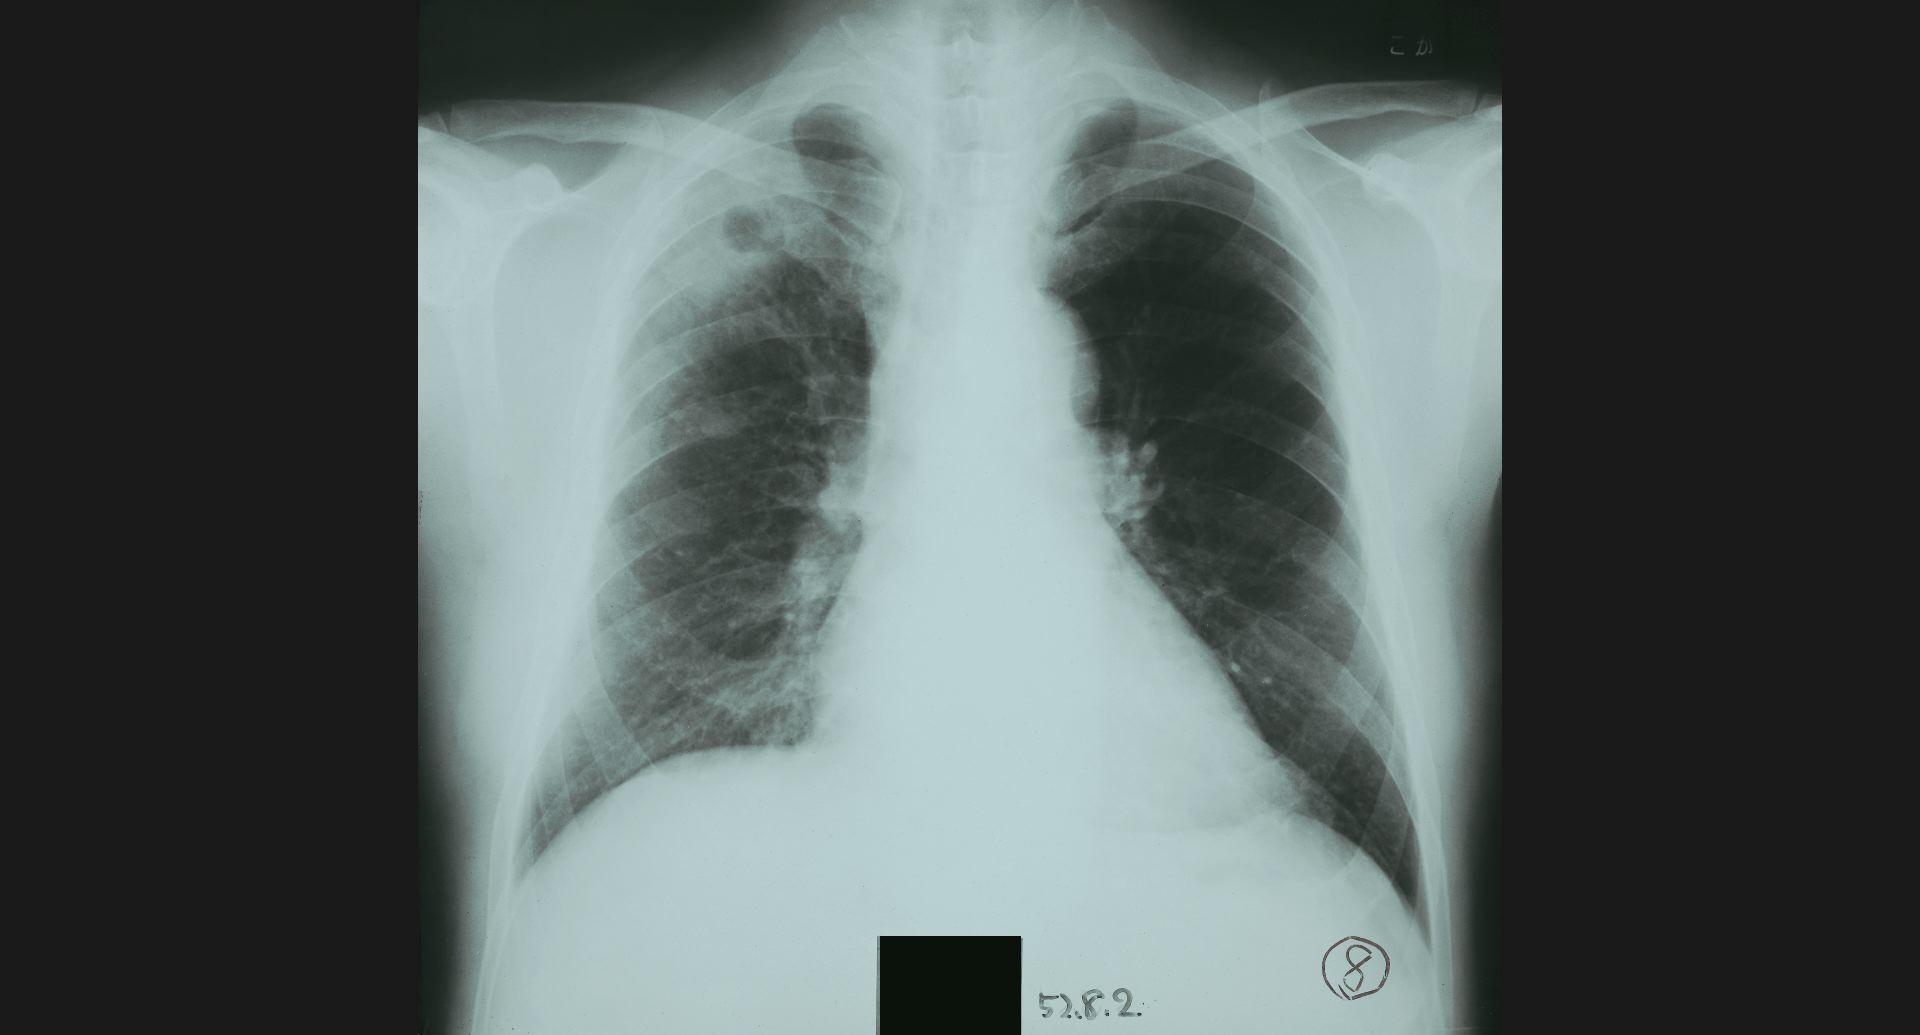

fig.1(117KB) :Alveolar microlithiasis

細かい肺病変、air bronchogram。